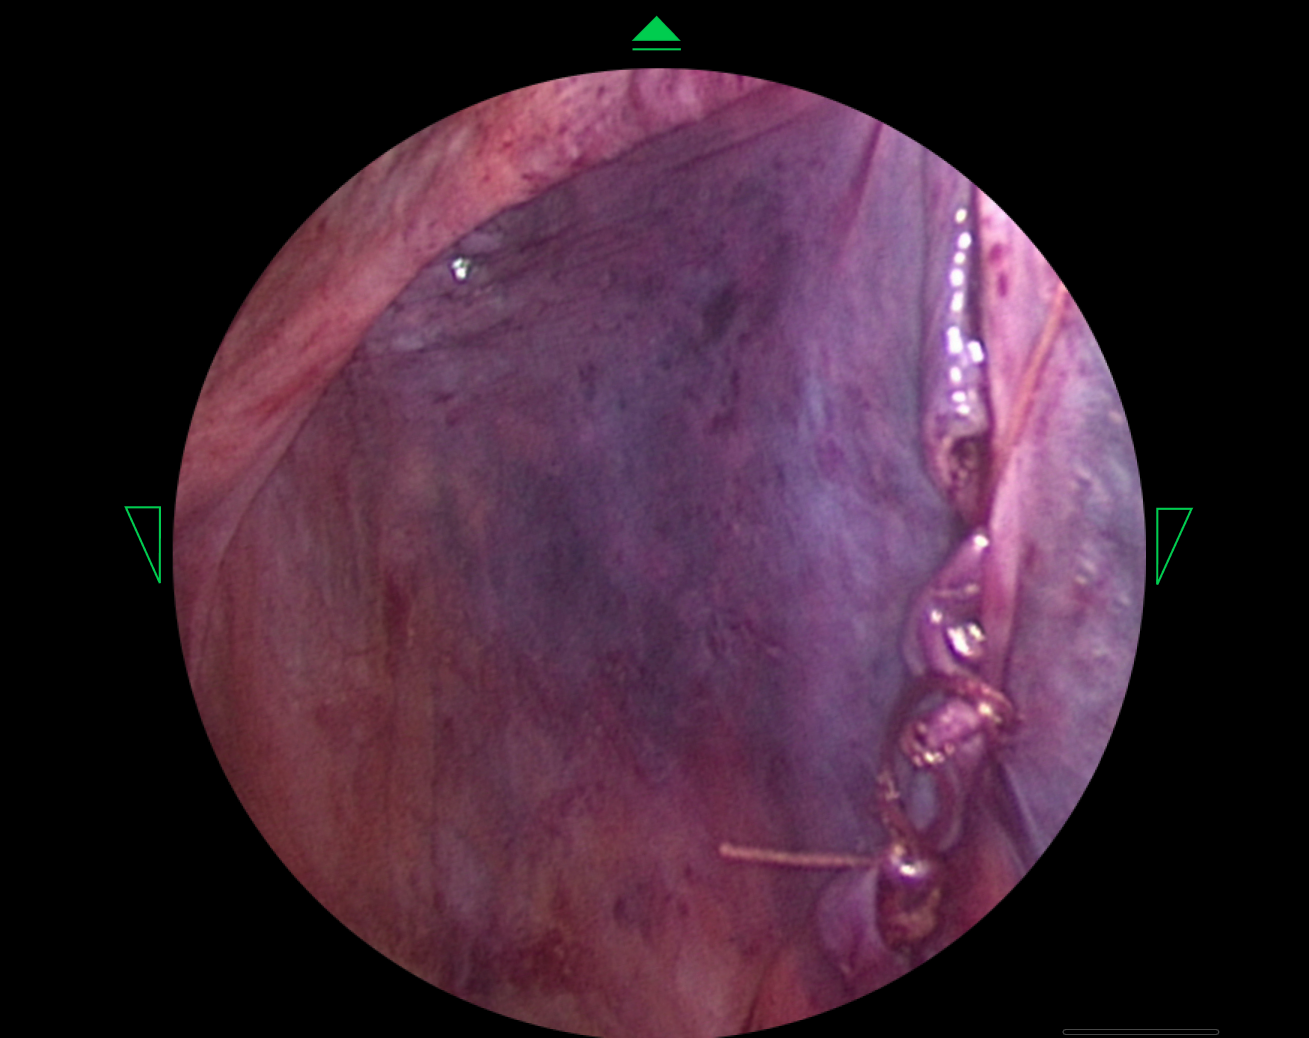

HUD Design: Surgery-Ready Interfaces

Operating rooms aren't like offices. I designed interfaces specifically for heads-up displays, considering lighting, distance, and the critical nature of surgical procedures.

- Created HUD displays that surgeons could actually use